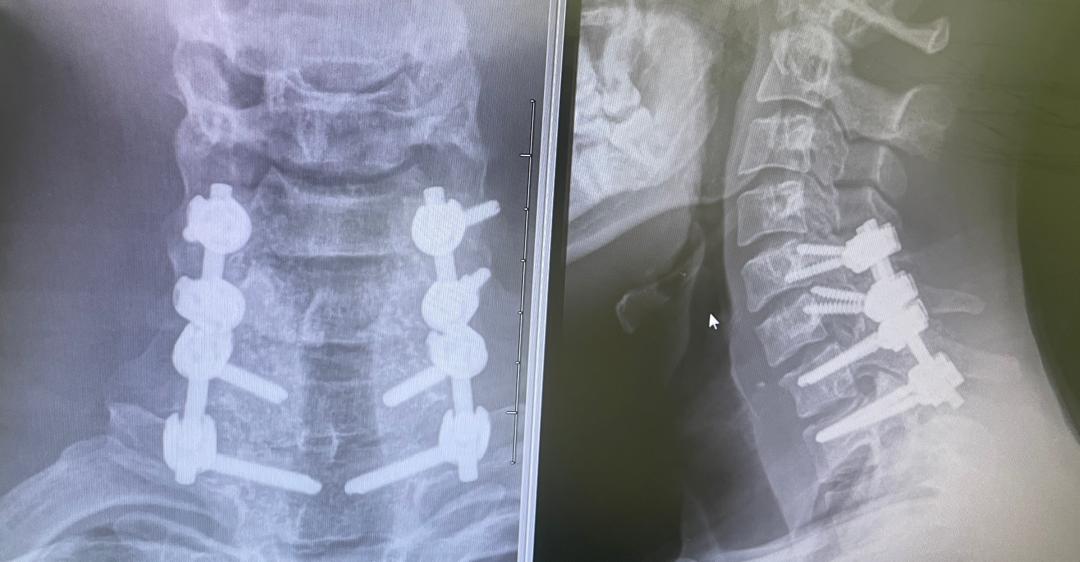

The Centre For Neuro-Oncologic and Spine Surgery (CNS) is a Gaborone-based Neurosurgical practice providing expert care for a wide scope of emergency and elective services. We have a special interest in minimally invasive brain tumor surgery and spine surgery.

Dr. B. A. Kgaodi is a neurosurgeon with subspecialty fellowship training in Spine surgery and a special interest in endoscopic pituitary surgery.

We have a special interest in minimally invasive brain tumor surgery and spine surgery.

When is spine surgery necessary?

Surgery is considered when conservative measures fail or if there’s significant nerve/spinal cord compression causing symptoms such as pain, weakness, numbness, or bowel/bladder changes.

MISS involves smaller incisions, minimal tissue disruption, and advanced tools to access the spine. It typically results in faster recovery, less post-op pain, and shorter hospital stays.